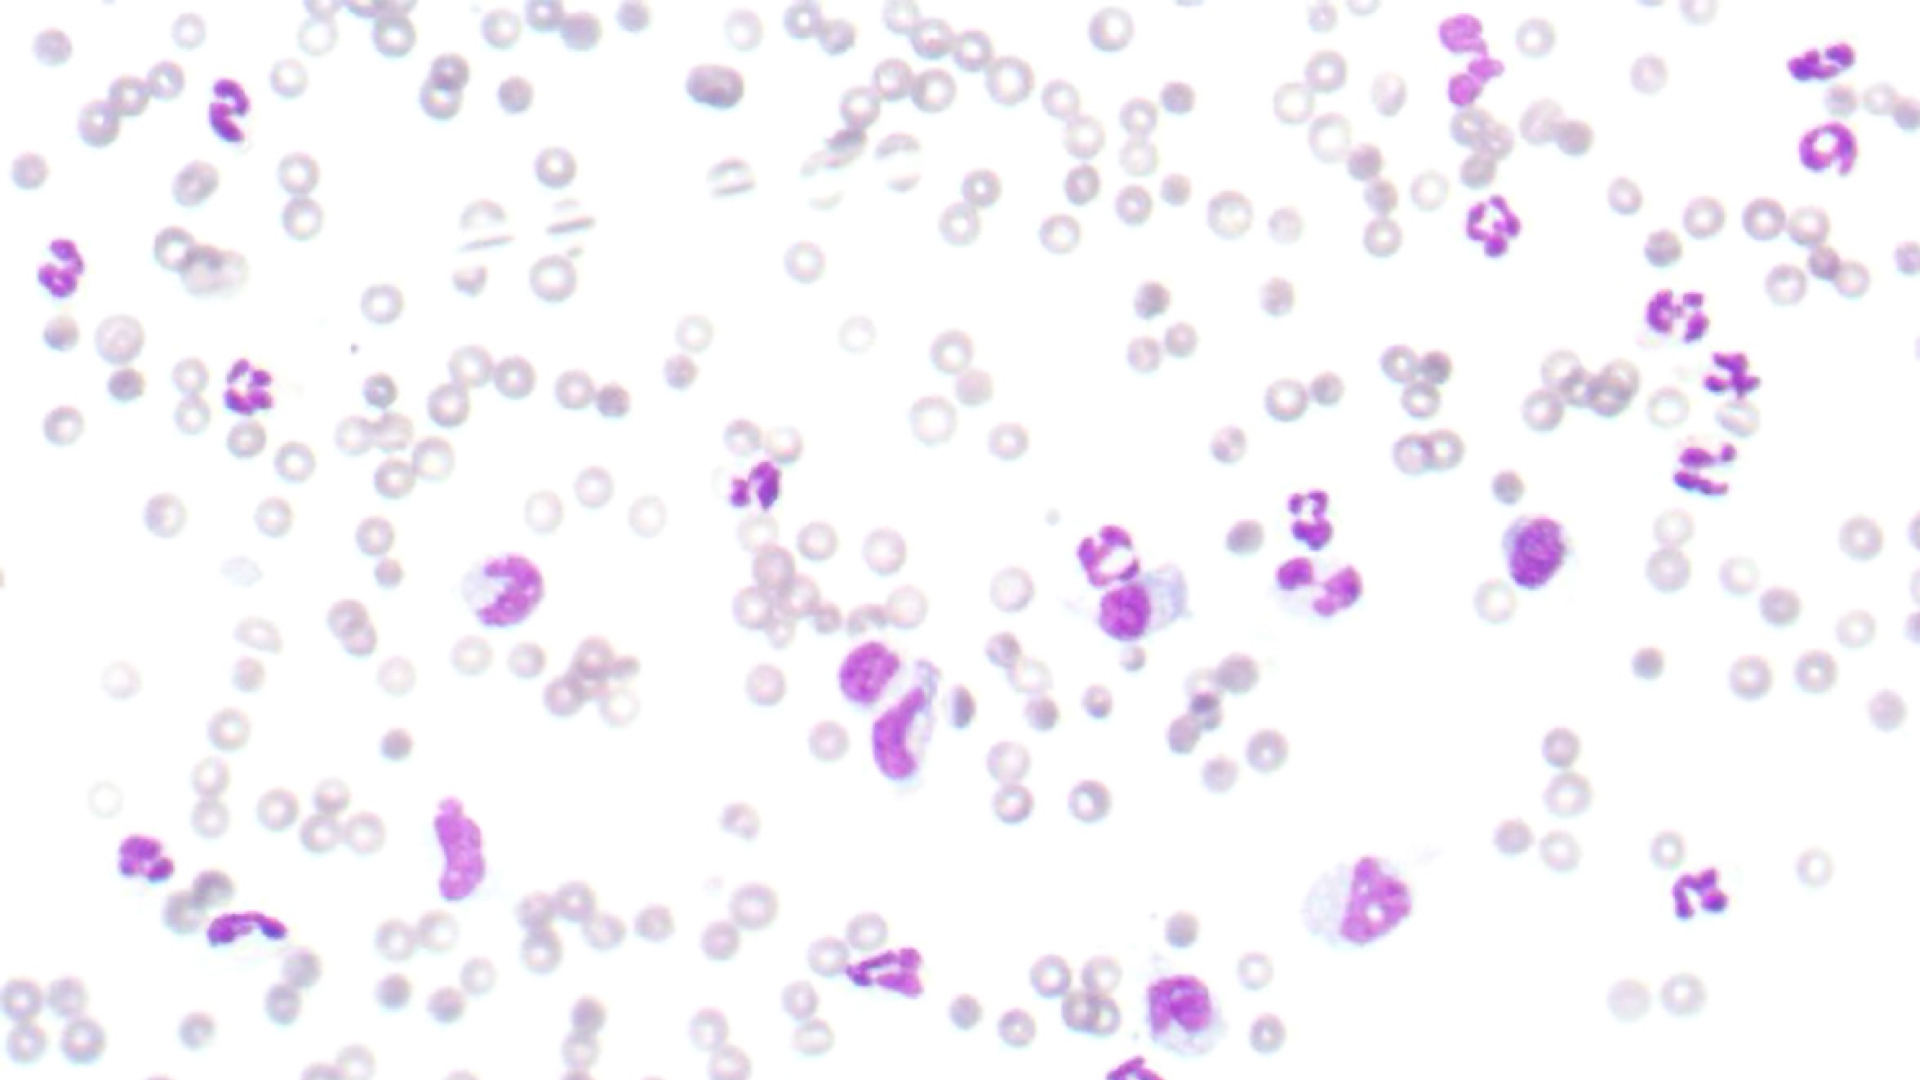

Bei der Blutchemie waren alle untersuchten -Organwerte in der Norm. Das Blutbild zeigte einen normalen Hämato-krit (42 Prozent), eine Thrombozytopenie (69 K/µL), eine Retikulozytose (137 K/µL) und eine Leukozytose (27 K/µL) mit Neutrophilie und Monozytose. Das C-reaktive Protein (CRP) war mit 162 mg/l (0–10) deutlich erhöht. Die Thrombozyten von Akiro wurden bereits bei vorhergehenden Untersuchungen mittels Blutausstrich kontrolliert und als Megathrombozyten und demnach als nicht pathologisch diagnostiziert. Die Röntgenuntersuchung des Thoraxes in zwei Ebenen erschien unauffällig (Abb. 1), wohingegen der Ultraschallbefund deutliche Veränderungen zeigte. Neben einem mittelgradigen Aszites war im kaudalen Abdomen eine circa sechs Zentimeter große, runde, inhomogene Masse mit gemischter Echogenität zu erkennen (Abb. 2). Dem ersten Anschein nach handelte es sich um eine Umfangsvermehrung der Milz, allerdings war keine Verbindung zu dieser auszumachen. Die restlichen Bauchorgane konnten gut abgegrenzt werden und zeigten sich sonographisch unauffällig. Das Punktat der freien Flüssigkeit war sero-sanguinös mit einer hohen Zellzahl und hohem Eiweißgehalt von 4,5 g/dl (Abb. 3). Demnach handelte es sich um ein Exsudat. Das zytologische Bild des Punktats zeigte eine sterile Entzündung. Der Hämatokrit des Punktats war bei zwölf Prozent.